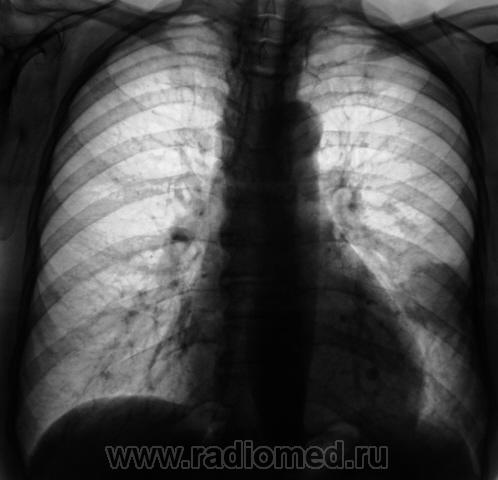

На сайте "Радиография", уважаемым Владимиром Борисовичем Серовым, выставлен интересный случай - круглая тень в нижнем легочном поле, зафиксированная на рентгенограмме органов грудной полости, произведенной в прямой стандартной проекции.

Сегодня исследовали пациента, с почти аналогичной "круглой тенью", правда, несколько больших размеров. При расшифровке цифровых флюорограмм "передвижного флюорографа", пациент "взят на контроль". Произведено стандартное дообследование - рентгенография в прямой и левой боковой проекциях. Пациент жалоб не предъявляет. Ниже представлены изображения рентгенограмм и их фрагментов с увеличением.

На мой взгляд, в данном случае симптоматика несколько иная(хотя рак лёгкого, то же не исключаеться):нет признаков лучистости, бугристости контуров образования( согласен с коллегами, в том случае скорее следует думать о перферическом раке лёгкого).Образование расположено паракостально( что не очень характерно для рака), какой-от тяж от образования  к диафрагме(?).Считаю что в обоих случаях показана КТ грудной клетки.

Родилась мысль об артерио-венозных аневризмах.